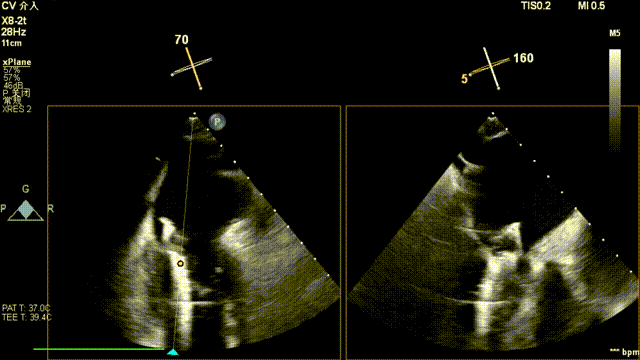

全麻后,二尖瓣夹合器系统在心前区的肋间切开3-4CM小切口,暴露心脏的心尖位置,送系统送入左心房,顺利到达病变二尖瓣区域。在经食道超声辅助下,术者通过反复评估二尖瓣反流位置、抓捕位置、反流程度,首先在2偏3区位置处于二尖瓣闭合线垂直进行巧妙夹合。在2区靠近3区位置处植入了1枚ValveClamp®MVC-IIf夹,最终评估评估反流降至轻度,平均跨瓣压差降至2mmHg,手术取得圆满成功。

术中超声(关键步骤)

最终在A3P2位置夹合,前叶夹合量10mm,后叶夹合量8mm,剩余瓣口面积3.45cm²,平均跨瓣压差2mmHg,反流基本消除。